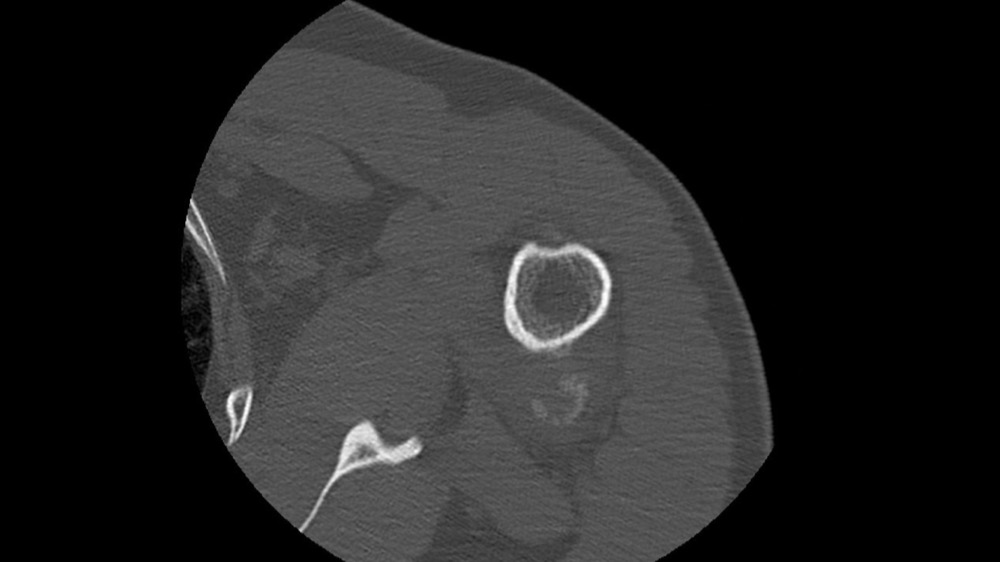

Bone Club

Gortais / Biyoukar / Miquel / Parlier-Cau 19/01/2022